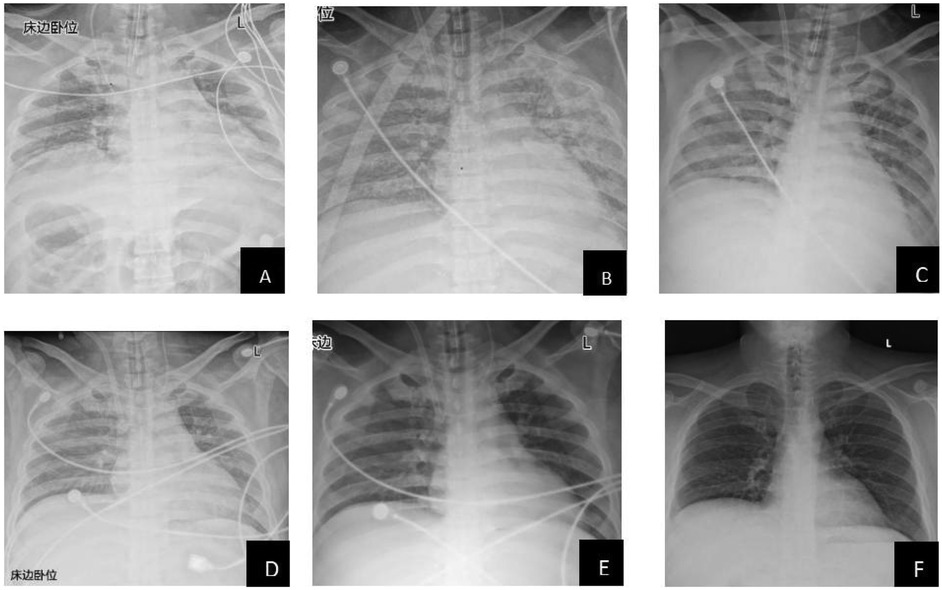

The patient's lung condition improved rapidly (as shown in Figure 1). ECMO was successfully weaned on postoperative day (POD) 4 (PaO2 129 mmHg on FiO2 40%), followed by extubation on POD 11 with intact neurological status. The patient was transferred from the ICU on POD 14 and discharged on POD 61 with normalized liver function (TBIL 22.2 μmol/L, ALT 214 U/L) and no infection recurrence. Three-month follow-up confirmed asymptomatic recovery, graft viability on ultrasound, and normalized AFP (12 μg/L). Key laboratory trends included bilirubin decline (peak 312.2 μmol/L pre-op → 70.6 μmol/L POD 7), renal recovery (Cr 157 → 64 μmol/L), and coagulopathy resolution (PT 26.3 → 16.8 s POD 5) (Table 2).

Figure 1. Radiological changes in the patient's lungs (A: preoperative; B: 1 day postoperatively; C: 2 days postoperatively; D: 3 days postoperatively; E: 4 days postoperatively; F: 9 days postoperatively). This study was approved by the relevant institutional review board/ethics committee, and informed consent was obtained from the patient.